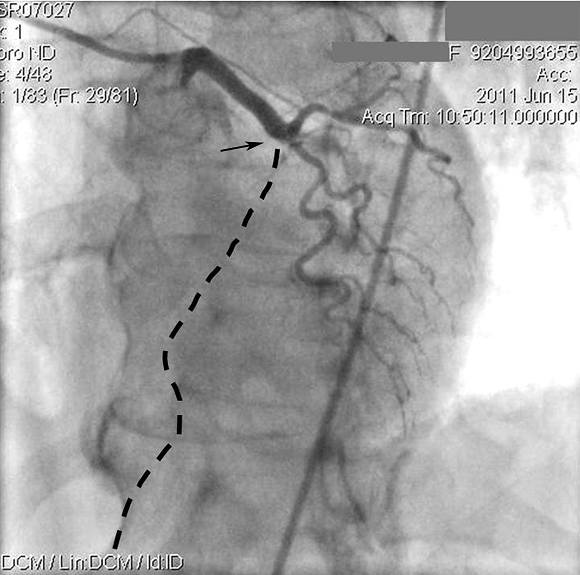

Вот так выглядели артерий сердца после диагностического исследования. Обратите внимание на закупорку главной артерии сердца прямо от начала (показана стрелкой). Ход этой артерии должен быть таким, как показывает пунктирная линия, однако, ее не видно, поскольку из-за закупорки кровь туда не поступает.

А это изображение тех же артерий, но их вид дается с другим углом зрения. Обратите внимание, какой большой участок артерии (пунктирная линия) выключен из кровотока.